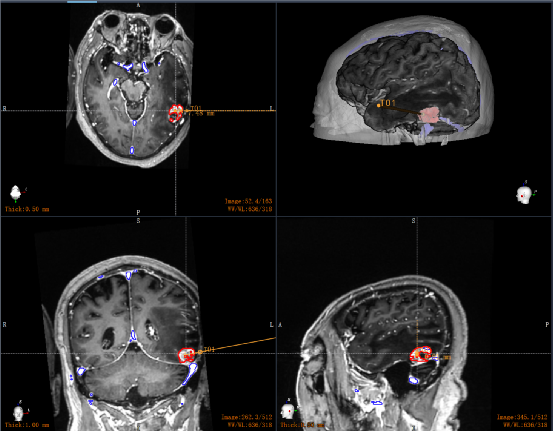

为尽量降低手术风险,减少术后并发症发生,孟辉主任医师团队术前采用神经外科手术机器人RM-100对患者影像资料多模态融合与分析,三维立体精确的显示肿瘤与周围正常脑组织、血管毗邻关系:肿瘤定位于左侧颞下回后部与梭状回之间,基底起源于小脑幕,边缘紧贴横窦末端,与下吻合静脉关系紧密。

图2 多模态影像融合后行肿瘤定位、手术路径规划(红色为肿瘤组织,蓝色为静脉窦,T01为手术入路)